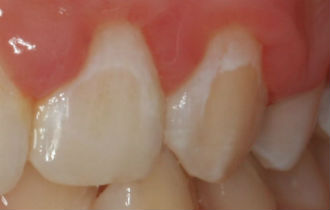

This decay is often referred to as white spot lesions which affects, according to a 2015 meta-analysis, nearly 70 per cent of people fitted with orthodontic braces*.

The problem areas are around the edges of the retaining brackets where plaque accumulates. Because of the wires and brackets it is difficult to keep the teeth clean. This results in many patients ending up with straight teeth after orthodontics but with blotchy marks that can affect their willingness to smile and reduce their self-confidence. This discolouration takes many months or even years to disappear.

The new bioactive bonding adhesive differs from the currently used materials by continuously releasing fluoride, calcium and phosphate to form fluorapatite. Fluorapatite will remineralise adjacent tooth surfaces and also reduce plaque formation around the orthodontic bracket, reducing the risk of initial decay seen as a chalky surface on the tooth enamel.

White spot lesions